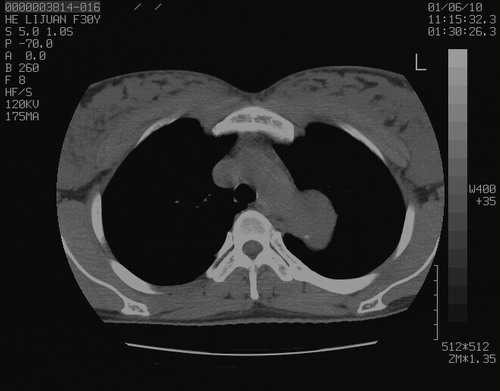

怀孕3个月时(2009-3至4月间),自述突感左侧前后胸疼痛1天,以前胸明显,随后偶感闷痛,余未见异

左肺尖脊柱旁沟肿块,境界清楚,边缘光滑,密度不均,内有多发点片状钙化,考虑良性肿瘤,骨软骨瘤或神经源性肿瘤可能,肺错构瘤不除外。

左后上纵隔见一类圆形肿块影,外侧边界清,密度不均匀,内可见点状钙化影,增强呈不均匀强化,考虑神经源性肿瘤可能。期待病理结果。